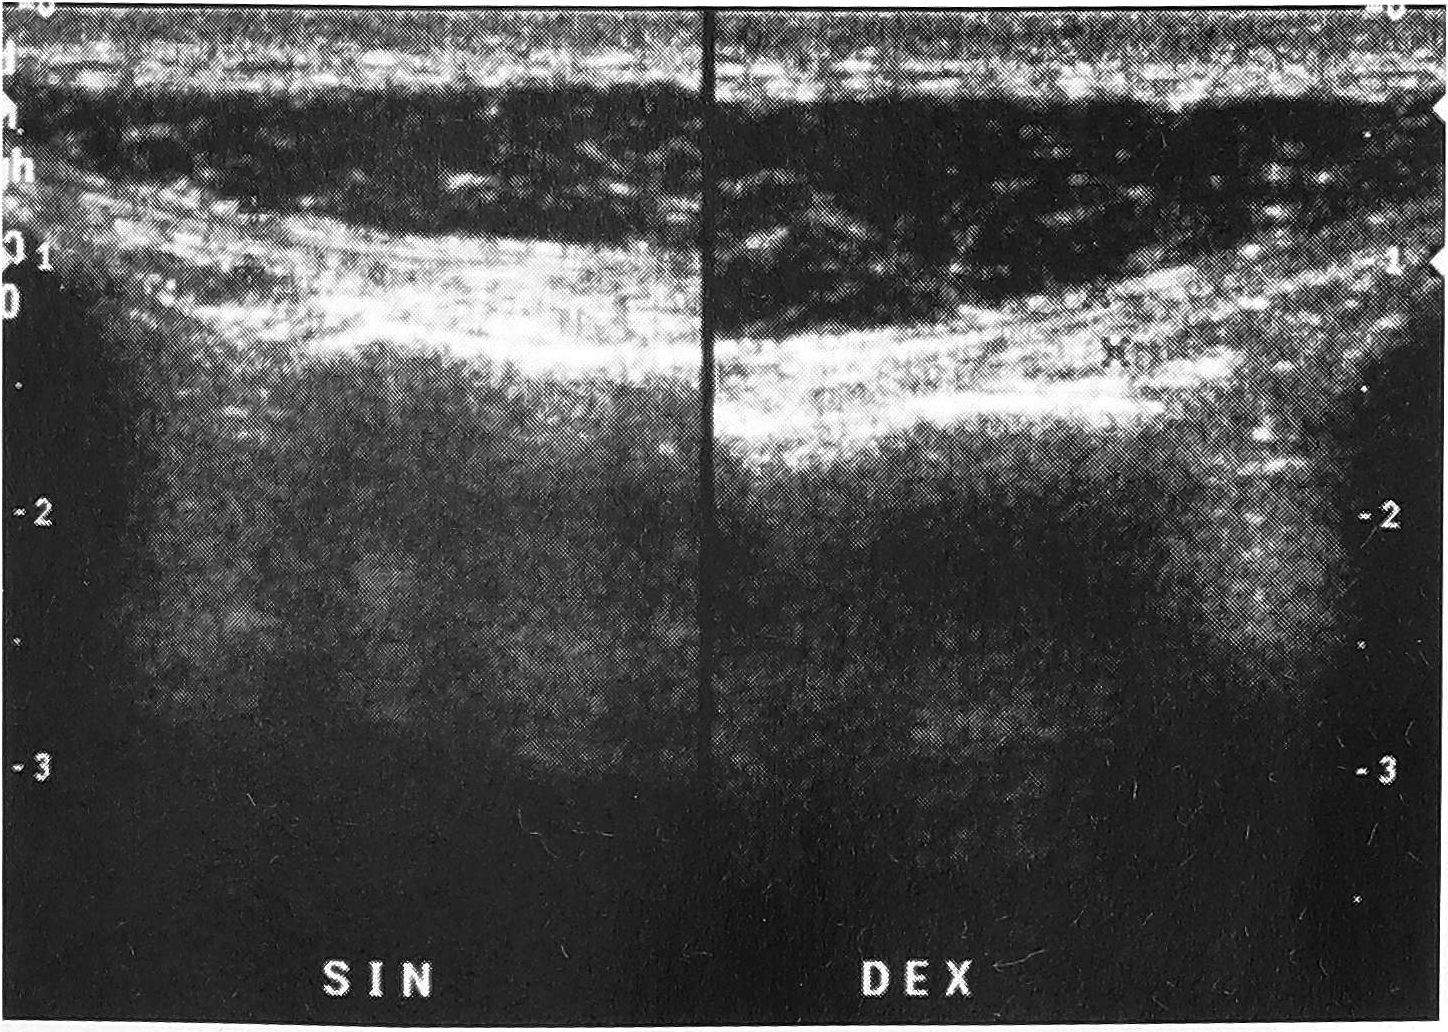

Небольшие протрузии дисков, медианные и парамедианные грыжи не влияли на кровоток. Значительное ослабление его обнаруживалось при заднебоковых протрузиях или грыжах (рис. 3). В 2 случаях при выраженных дегенеративных изменениях диска отмечено врастание в него сосудов.

Рис. 3. Импульсно-волновая допплерография в режиме дуплексного сканирования: а — снижение скорости кровотока на стороне заднебоковой грыжи; б — нормальный кровоток на другой стороне.